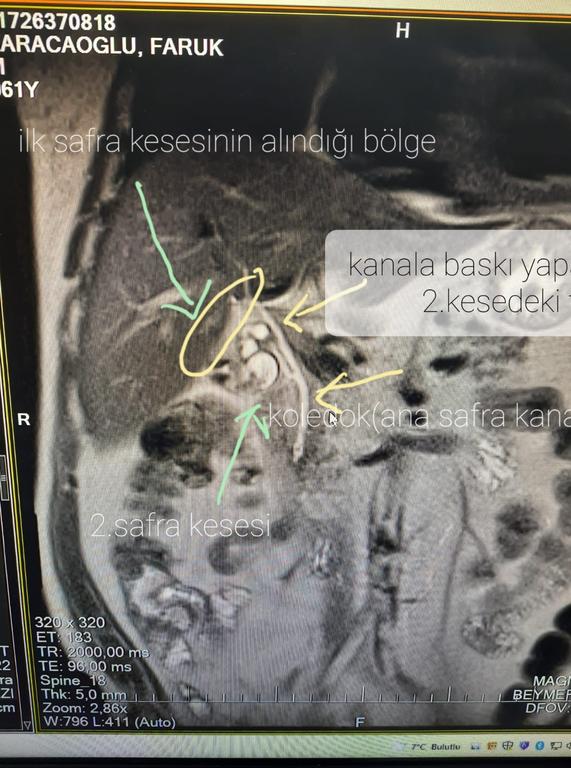

Safra kesesinin normal olanının ilk alındığını belirten Dr. Koçberber, “Safra kesesinin hem kanalı hem de damarının çift olması nadir bir durum. Yıllar önce benim bir hastamın da başına gelmişti. Bu hastamız 12-13 sene önce başarılı bir şekilde safra kesesi ameliyatı geçirmiş. Safra kesesinin orijinal yerinde olanı alınmış. Ancak normal yerinde olmayan arka tarafta yeni bir kanalı olarak ayrı damarı olan daha farklı ikinci safra kesesi varmış. Yıllar içerisinde bu kesenin içerisinde taşlarda oluşmuş. Hastamız farklı semptomlarla doktorlara gitmiş ama safra kesesi alındığı için ilaç tedavisiyle geçiştirilmiş” dedi.

İlerleyen süreçte ikinci safra kesesinin önemli etkenlere neden olabileceğini ifade eden Dr. Koçberber, “Hastamızı dün kapalı bir şekilde ameliyat ettik ve bu ikinci safra kesesini biraz zorda olsa aldık. Bizde doktorlar olarak safra kesesinde ameliyat oldu diye ayrı bir safra kesesi olduğunu düşünüp buna göre hastada ileri tetikleri yapmamız gerekiyor. Ana safra kanalı dediğimiz poledok kanalına baskı yapıp neredeyse çürümesine, tıkanıklığına sebep olup hayati tehlikede oluşturabilirdi” diye konuştu.